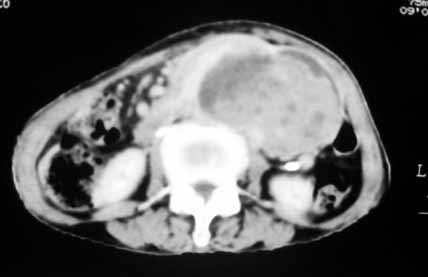

以下是引用天南地北在2007-4-30 17:42:00的发言:[br]增强扫描显示腹主动脉给包绕、推移。肿块不规则强化,[br]修正我在平扫的诊断[br]支持考虑:间叶源性肿瘤可能性大

以下是引用余辉在2007-4-30 18:01:00的发言:[br]病灶前方的条状增强影是什么?若是胰腺,位置似乎有点低,若是十二指肠,似乎又不诫该是那样强化,姑且将其看作胰腺吧,那么考虑来源于胰腺粘液囊腺瘤可能性大,其次考虑来源于肠系膜或者后腹膜的肿瘤如平滑肌肉瘤,异位嗜铬细胞瘤及淋巴瘤等。

以下是引用zyx168在2007-4-30 23:24:00的发言:[br]考虑:间叶源性肿瘤可能性大